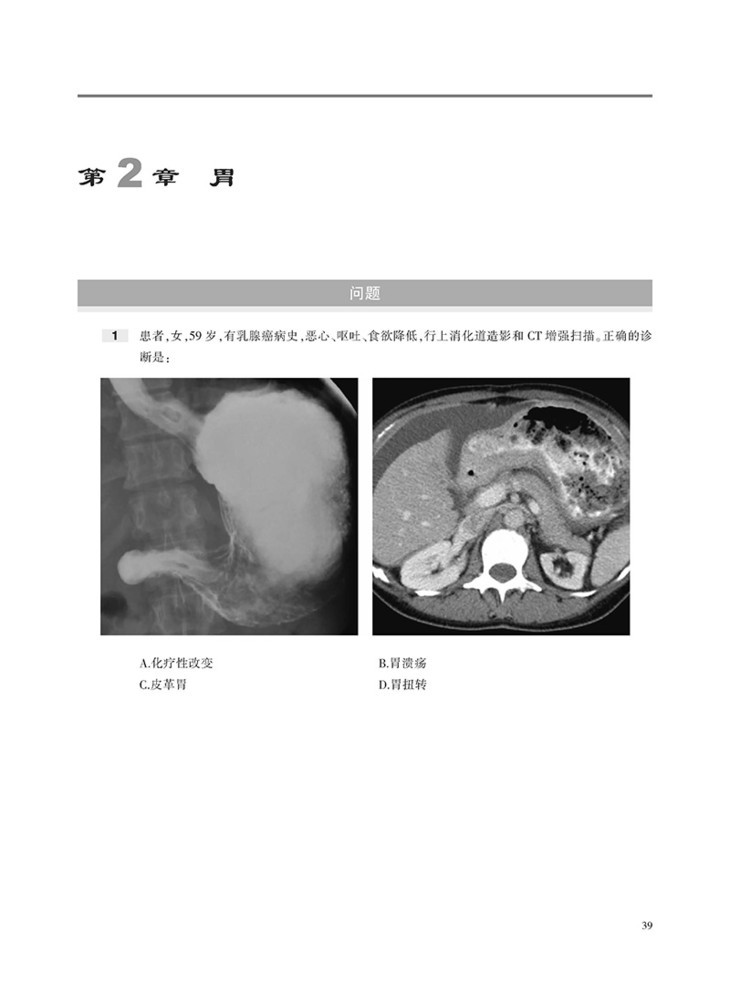

本书内容采用问答体例,首先给出患者病史和影像图片,然后列出问题和选项,便于读者独立思考,选择答案。各章末附有选择题答案和解析,正确选项和错误选项均有详细的注释,有助于读者加深理解和记忆。

囊括数百幅高清图像,直观显示病变的形态与特点等。